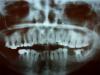

Лана1 Опубликовано 11 ноября, 2010 Поделиться Опубликовано 11 ноября, 2010 Подскажите, пожалуйста, по снимку, какие зубы следует перелечить, готовлюсь ставить брекеты.И подскажите - какой зуб лучше удалить - 24, 25 или 26 для орто-лечения, какой более разрушен?Ортодонт с удалением окончательно не определился. Ссылка на комментарий

Мартовский Опубликовано 11 ноября, 2010 Поделиться Опубликовано 11 ноября, 2010 Подскажите, пожалуйста, по снимку, какие зубы следует перелечить, готовлюсь ставить брекеты.И подскажите - какой зуб лучше удалить - 24, 25 или 26 для орто-лечения, какой более разрушен?Ортодонт с удалением окончательно не определился.Такие решения по панорамному снимку не принимаются. Нужны фото моделей, ТРГ, фото зубов в прикусе и жевательной поверхности, и открыть тему в разделе "ортодонтия". Но тогда наши заключения будут предположительными, потому что мы не сможем виртуально посчитать расстояния на ваших моделях. Ссылка на комментарий

Лана1 Опубликовано 17 ноября, 2010 Автор Поделиться Опубликовано 17 ноября, 2010 (изменено) Мартовский, спасибо ) Все-таки еще раз попробую спросить. Какие зубы стоит перелечить? 24 уже удален, 26 - пломба заменена. Какие еще? Изменено 17 ноября, 2010 пользователем Лана1 Ссылка на комментарий

Salma Опубликовано 17 ноября, 2010 Поделиться Опубликовано 17 ноября, 2010 Мартовский, спасибо ) Все-таки еще раз попробую спросить. Какие зубы стоит перелечить? 24 уже удален, 26 - пломба заменена. Какие еще? не плохо было бы посмотреть прицельные снимки зубов 18, 17,38, 37, 45 46. Ссылка на комментарий